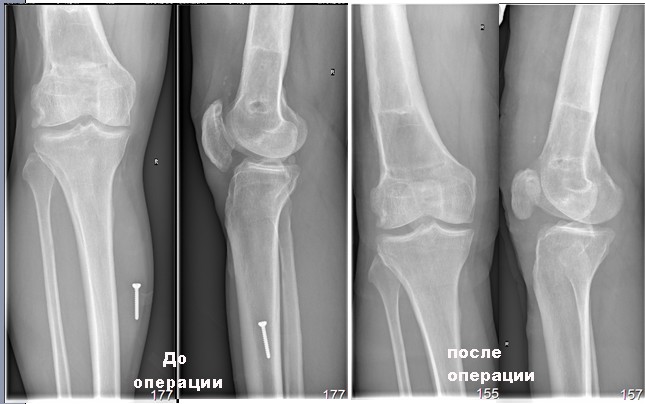

спешу  поделиться  результатом операции, проведенная 25/01/2012 года. Выполнен  передний  срединный доступ к  коленному  суставу  длиной до 8 см, полость коленного  сустава  вскрыта  медиально от  надколенника, выделилось до 20 мл синовиальной  жидкости. Надколенник вывирнут. Суставная поверхность  надколенника склерозирована,

резко слерозирован (до каменной плотности) верхне-наружный квадрант наколенника. Хрящ на надколеннике практически отсутствовал. Остеофиты по  всей  окружности надколенника (надколенник имел  вид  "блюдца" из-за этих сотеофитов). Жировое тело  гипртрофировано. Хрящ  на мыщелках бедра достаточно сохранный, хотя  не  идеальный. В межмыщелковом  простарнстве бедра (спереди крестообразных  связок)остефиты.

операцию по артропластике переднего отдела коленного сустава: моделирующая резекция нижнего полюса надколенника для уменьшения его вертикального размера и уменьшения гиперпрессии на фасетку бедренной кости. Придать надколеннику сесамовидную форму и борозде - соответствующее углубление." Мы  практически выполнили все то, что нам рекомендовал А. Каземирский.

Сегодня  объем  движений: сгибание 60 градусов, разгибание  180. Конечно, движения  в  коленом  суставе пока  болезненны, особенно в  области резецированного  дистального  полюса  надколенника.  Будем  следить за  реабилитацией данного  пациента.

Прилагаю  картинки до и  после.